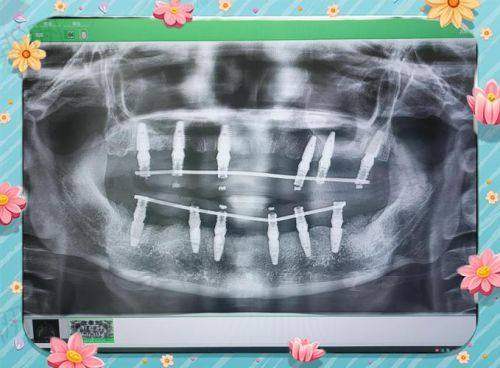

設備要先進:要有CBCT三維掃描儀(香港诊所基本都有,但深圳部分細诊所仲用傳統X光,唔夠精準),3D導板種植(減少手術風險);

植牙技術:All - on - 4全口,香港價格(HKD):15萬 - 35萬,適合人群:牙槽骨條件中等、預算中高嘅人,特點:上下各4顆種植體,穩定性夠,恢復快

植牙技術:All - on - 6全口,香港價格(HKD):18萬 - 40萬,適合人群:想更穩定、經常食硬嘢嘅人,特點:上下各6顆種植體,承重更好,適合食牛腩、蘋果

植牙技術:穿顴穿翼全口,香港價格(HKD):35萬 - 60萬,適合人群:牙槽骨嚴重吸收、無法植骨嘅長輩,特點:直接打釘入顴骨,唔使植骨,手術難度高